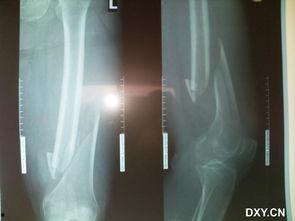

首先,让我们来了解一下什么是骨折。骨折,简单来说,就是骨头断裂了。这种断裂,可能是由于外力撞击,也可能是由于骨质疏松等原因。而骨折的痛苦,可不是一般的大哦!

想象当你突然感到一阵剧痛,骨头像被撕裂了一般,那种感觉,简直无法用言语来形容。而骨折后的恢复过程,更是漫长而痛苦。据数据显示,骨折后,患者需要平均花费6个月的时间来恢复。